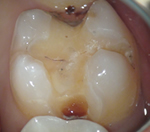

上のような小さな歯が、マイクロスコープではこのように見えています。

むし歯の治療(カリエス処置)

指の先ほどの歯の中の、むし歯の部分だけを除去しなければなりません。

むし歯の部分を取り損ねたら再発し、削り過ぎると歯を弱くしてしまうので、注意力と集中力が必要です。

マイクロスコープを用いれば視野を拡大して見られるため、健康な歯を痛めずむし歯の部分だけを除去できます。